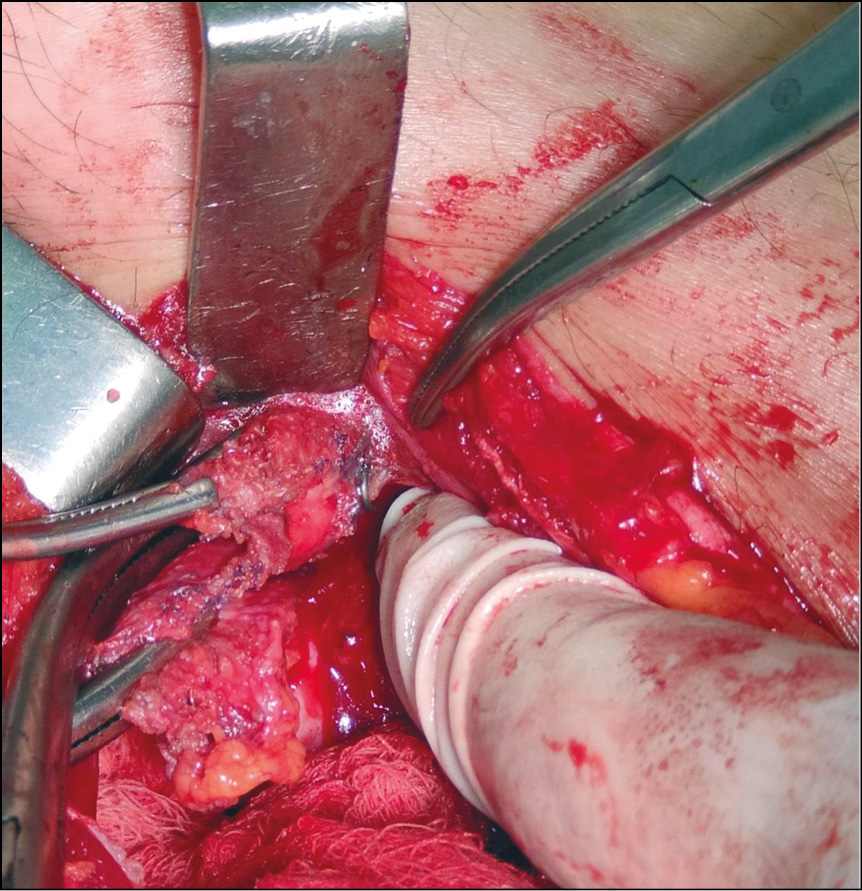

Компьютерная томография: явление симфизита с наличием инфильтрата в области симфиза, распространяющегося на переднюю стенку мочевого пузыря. В паховой области справа имеется сетчатый имплантат с множественными (№ 22) титановыми такерами (рис. 1).

Рис. 1. Пациент С., 52 года: компьютерная томография органов брюшной полости и малого таза

Примечание. Передняя и боковая проекция: осложнение после трансабдоминальной периперитонеальной пластики. В правой паховой области лоцируются множественные такеры крепления сетчатого имплантата.